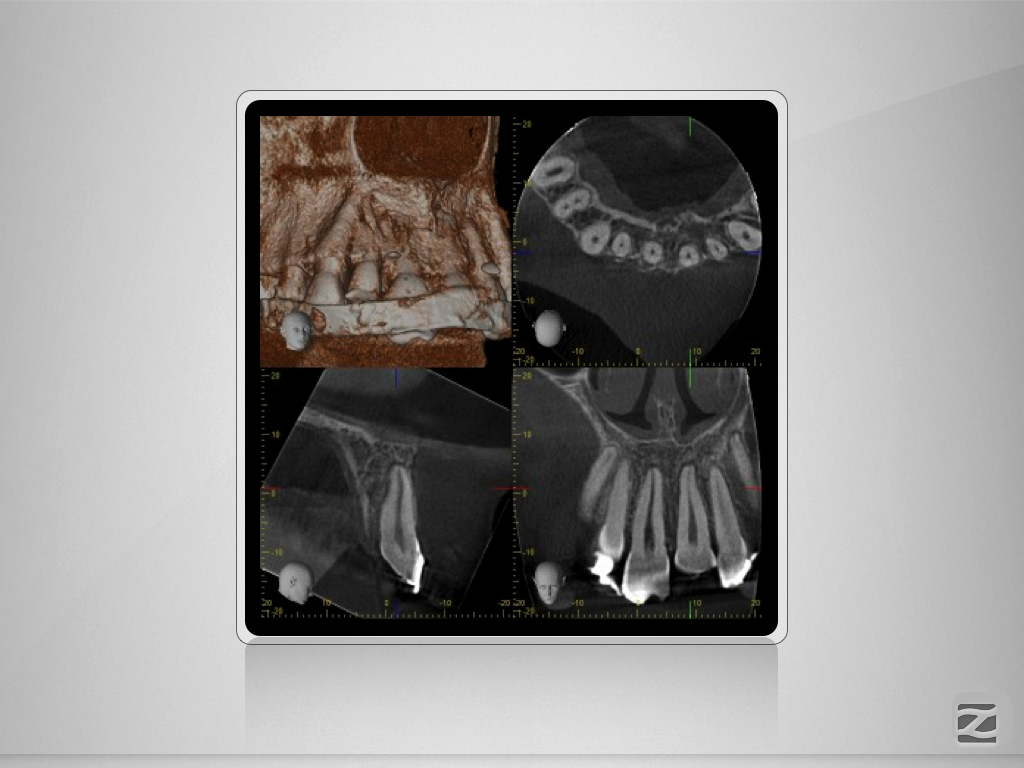

Multitrauma D.011

Mehrfach-Trauma